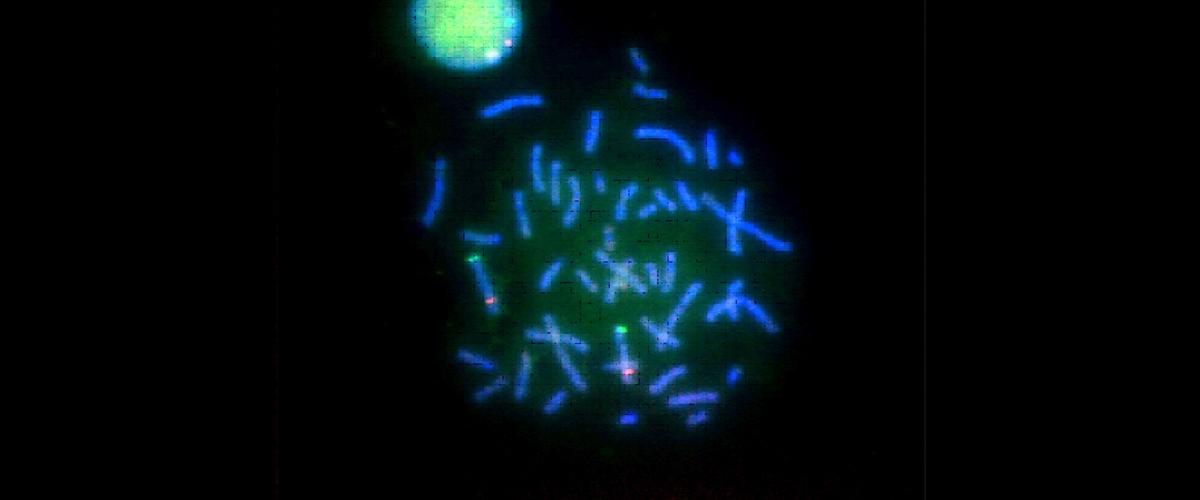

Из предыдущих исследований известно, что мужчины чаще болеют раком по сравнению с женщинами, однако причины этого до сих пор плохо изучены. Новое исследование международной группы ученых указывает, что ключевым фактором могут быть функциональные нарушения у генов в Y-хромосоме — половой хромосоме мужчин.

Риск рака увеличивался, если в Y-хромосоме нарушалась функция шести ключевых генов, показали наблюдения.

Эти гены участвуют в регуляции клеточного цикла, и нарушения могут привести к развитию опухоли, объяснили авторы. Интересно, что копии генов также присутствуют и на Х-хромосоме. Если и эти копии мутируют в тех же клетках, то защита от рака полностью теряется.